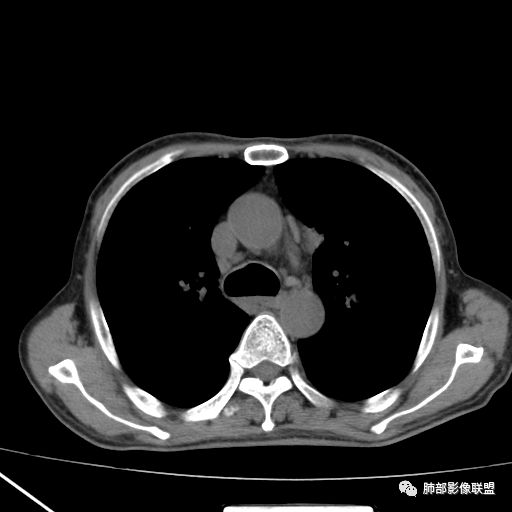

2019.08.24:胸部CT增强扫描:左肺上叶纵膈旁软组织结节影,双肺弥漫性小结节及细网状影,纵膈淋巴结肿大,心包积液,肝左叶散在低密度影。(没见片子)

现病史:患者于2个月前无明显诱因出现咳痰、咳痰,咳白粘痰或黄痰,有时痰中带血,伴发热,最高体温40.5度,多于下午起热,伴乏力盗汗,有时恶心呕吐,先后至日照市中心医院及青岛大学附属医院住院治疗,给予哌拉西林钠他唑巴坦及拜复乐抗炎,氟康唑抗真菌及对症支持治疗,患者入院检查痰培养(2019-09-08青岛大学附属医院)肺炎克雷伯菌。骨髓穿刺(2019-09-10青岛大学附属医院)检出1.5%异常浆细胞,胞浆kappa单克隆阳性。胸部CT(2019-08-24青岛大学附属医院)左肺上叶软组织影,双肺弥漫小结节并细网状影,纵膈淋巴结肿大,心包积液。自发病来,饮食睡眠差,体重较前下降约15斤。

2019-10-20复查CT如下:

10月20日的CT其实是抗痨治疗近1月复查的CT。患者来我院后抗痨治疗体温下降,症状明显好转。

急性血行播散型肺结核  两肺广泛分布粟粒大小的结节状密度增高影,具有大小均匀、分布均匀、密度均匀的典型“三均匀”特征,注意急性血播病灶非常小,一般粟粒影直径1~2mm。

病灶密集者出现肺外围血管影不清或减少。

发热初期肺部可缺乏典型影像学改变,1到2周后出现的广泛粟粒结节对诊断具有高度提示作用!

重视肺外病变的检查,如肝脏、眼底,以及神经系统的检查。